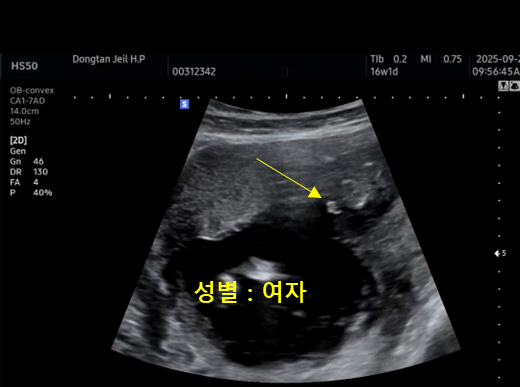

| 성별 | 여자 | - | 화면에서 확인 |

그리고 이번에 성별도 여자아이라고 알려주셨어요! 물론 아직 더 지켜봐야 하긴 하지만, “딸이에요”라는 말이 들리니까 갑자기 아기가 더 가까이 느껴지고, 이름도 막 떠올려보게 되더라고요.